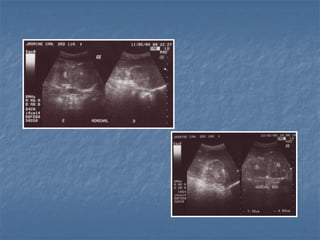

Hiperplasia adrenal bilateral

Hiperplasia adrenal unilateral

 Hiperadrenocorticismo

 Hipofisário dependente: há um aumento

bilateral (80% dos casos!), pode ser

simétrico ou assimétrico

* Medida normal de espessura menor que 0,74cm

cães adultos

 Hiperadrenocorticismo  Hipofisáriodependente: há um aumento bilateral (80% dos casos!), pode ser simétrico ou assimétrico * Medida normal de espessura menor que 0,74cm cães adultos